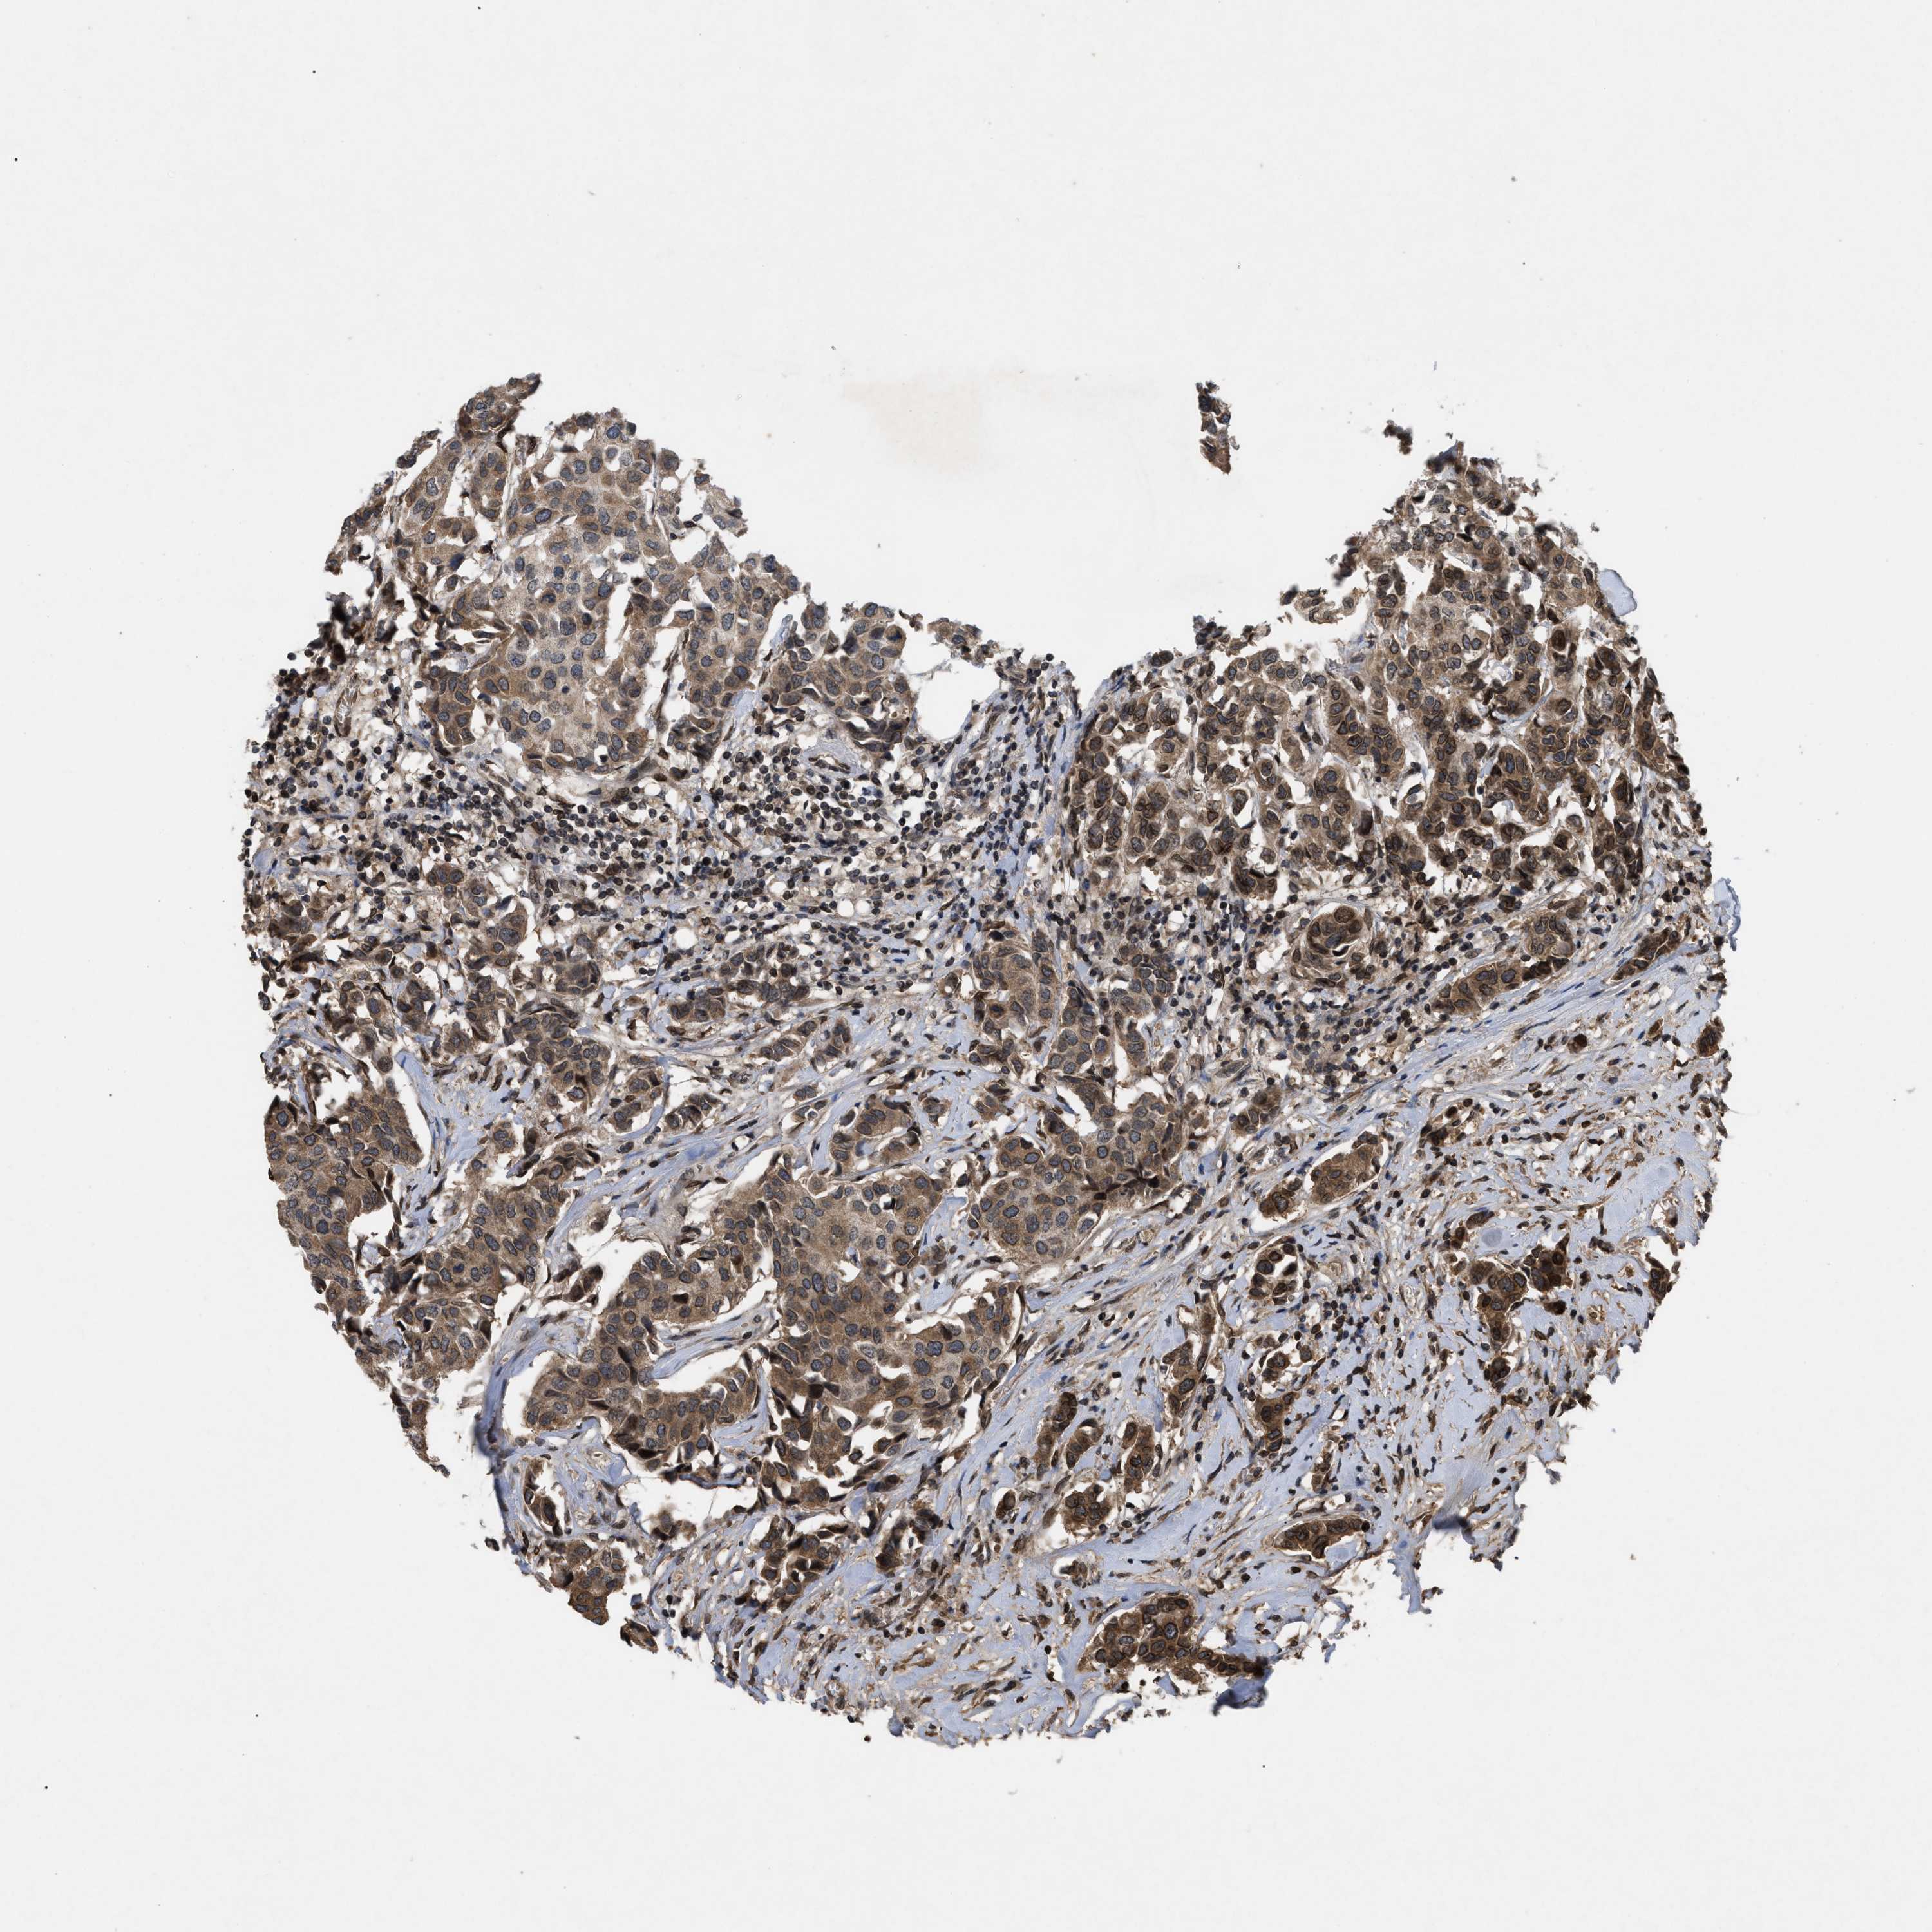

BRCA TCGA BRCA VALIDATION PROTEIN EXPRESSION